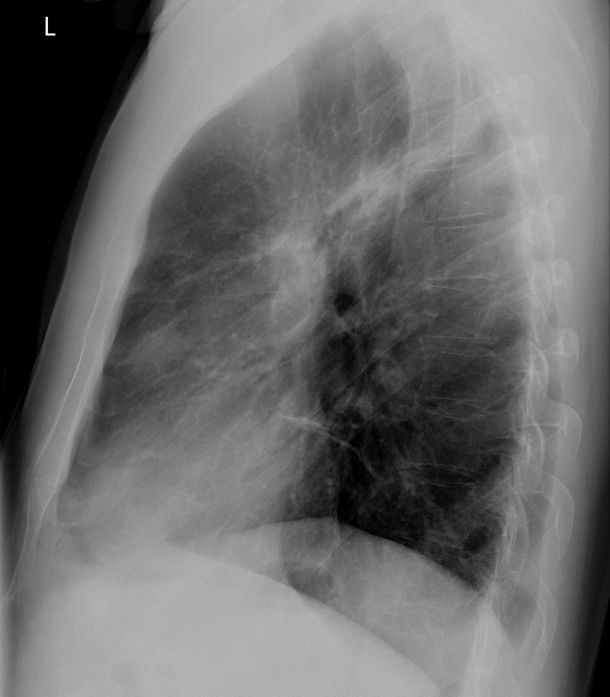

Spomenuti monolog nije dio izložbe, jer je izložba u potpunosti fotografska: od rendgenske snimke pluća i lica pokrivenog maskom za kisik, preko prikaza hrane i bolničkog pribora, do krošnji koje vidi kroz prozor ili obasjane bolničke zgrade noću, Petković na nenasilni i jezgrovit način šalje upozorenje.